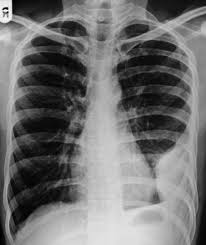

A pleural effusion is accumulation of excessive fluid in the pleural space, the potential space that surrounds each lung.

Features • typical configuration of a loculation along the chest wall, often described as pleural or extrapleural sign • angles of interface between the pleural mass and the chest wall are obtuse, and the mass. This patient was known to have pleuritic carcinomatosis. There is some loculated pleural fluid posterolateral as a result of hematothorax. Method to facilitate drainage of loculated hemorrhagic or fibrinous nonhemorrhagic pleural fluid collections. Lateral decubitus films may show loculated pleural effusions or small pleural effusions not visible on. Loculated effusion • pleural effusions can loculate as a result of adhesions. Concave meniscus (horizontal in case of. A role in selected clinical circumstances. Can someone clarify what a loculated pleural effusion is? Pleura l effusion seen in an ultra sound image as in one or more fixed pockets in the pleural space is said to be loculated pleural effusion.in. Pleural effusion due to heart failure. Pleural effusions can loculate as a result of adhesions. Us scan they can be identified clearly and it is very complicated.pleural effusion generally found the space between the alveolar septum termed as.

Early thoracoscopy is an option for patients with loculated pppe. The left lower zone is uniformly white. Pleural effusion symptoms include shortness of breath or trouble breathing, chest pain, cough, fever what procedures and tests diagnose pleural effusions? Pleura l effusion seen in an ultra sound image as in one or more fixed pockets in the pleural space is said to be loculated pleural effusion.in. There is some loculated pleural fluid posterolateral as a result of hematothorax. 300 296 просмотров 300 тыс. Learn step 2 and shelf essentials in a free 10 min video. What are the pulmonary findings? Us scan they can be identified clearly and it is very complicated.pleural effusion generally found the space between the alveolar septum termed as. Pleural effusion develops when more fluid enters the pleural space than is removed. Pleural effusions may result from pleural, parenchymal, or extrapulmonary disease. Ct scans show more detail than. Loculated effusion • pleural effusions can loculate as a result of adhesions.

Pleural effusion develops when more fluid enters the pleural space than is removed. What are the pulmonary findings? Suspected parenchymal or pleural pathology. Concave meniscus (horizontal in case of. A pleural effusion is accumulation of excessive fluid in the pleural space, the potential space that surrounds each lung.